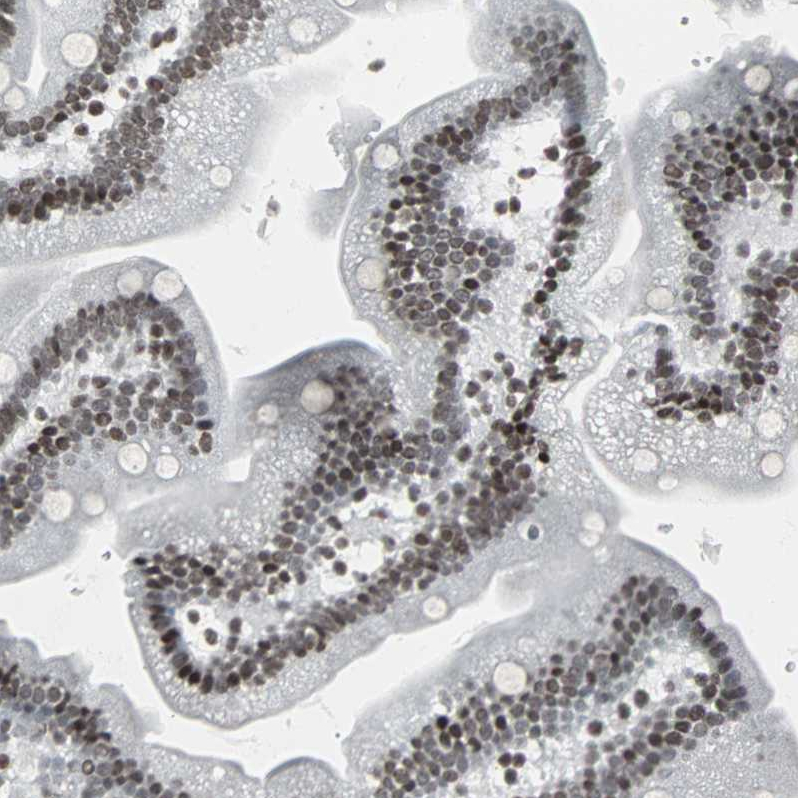

Immunohistochemical staining of human bone marrow shows strong nuclear positivity in hematopoietic cells.